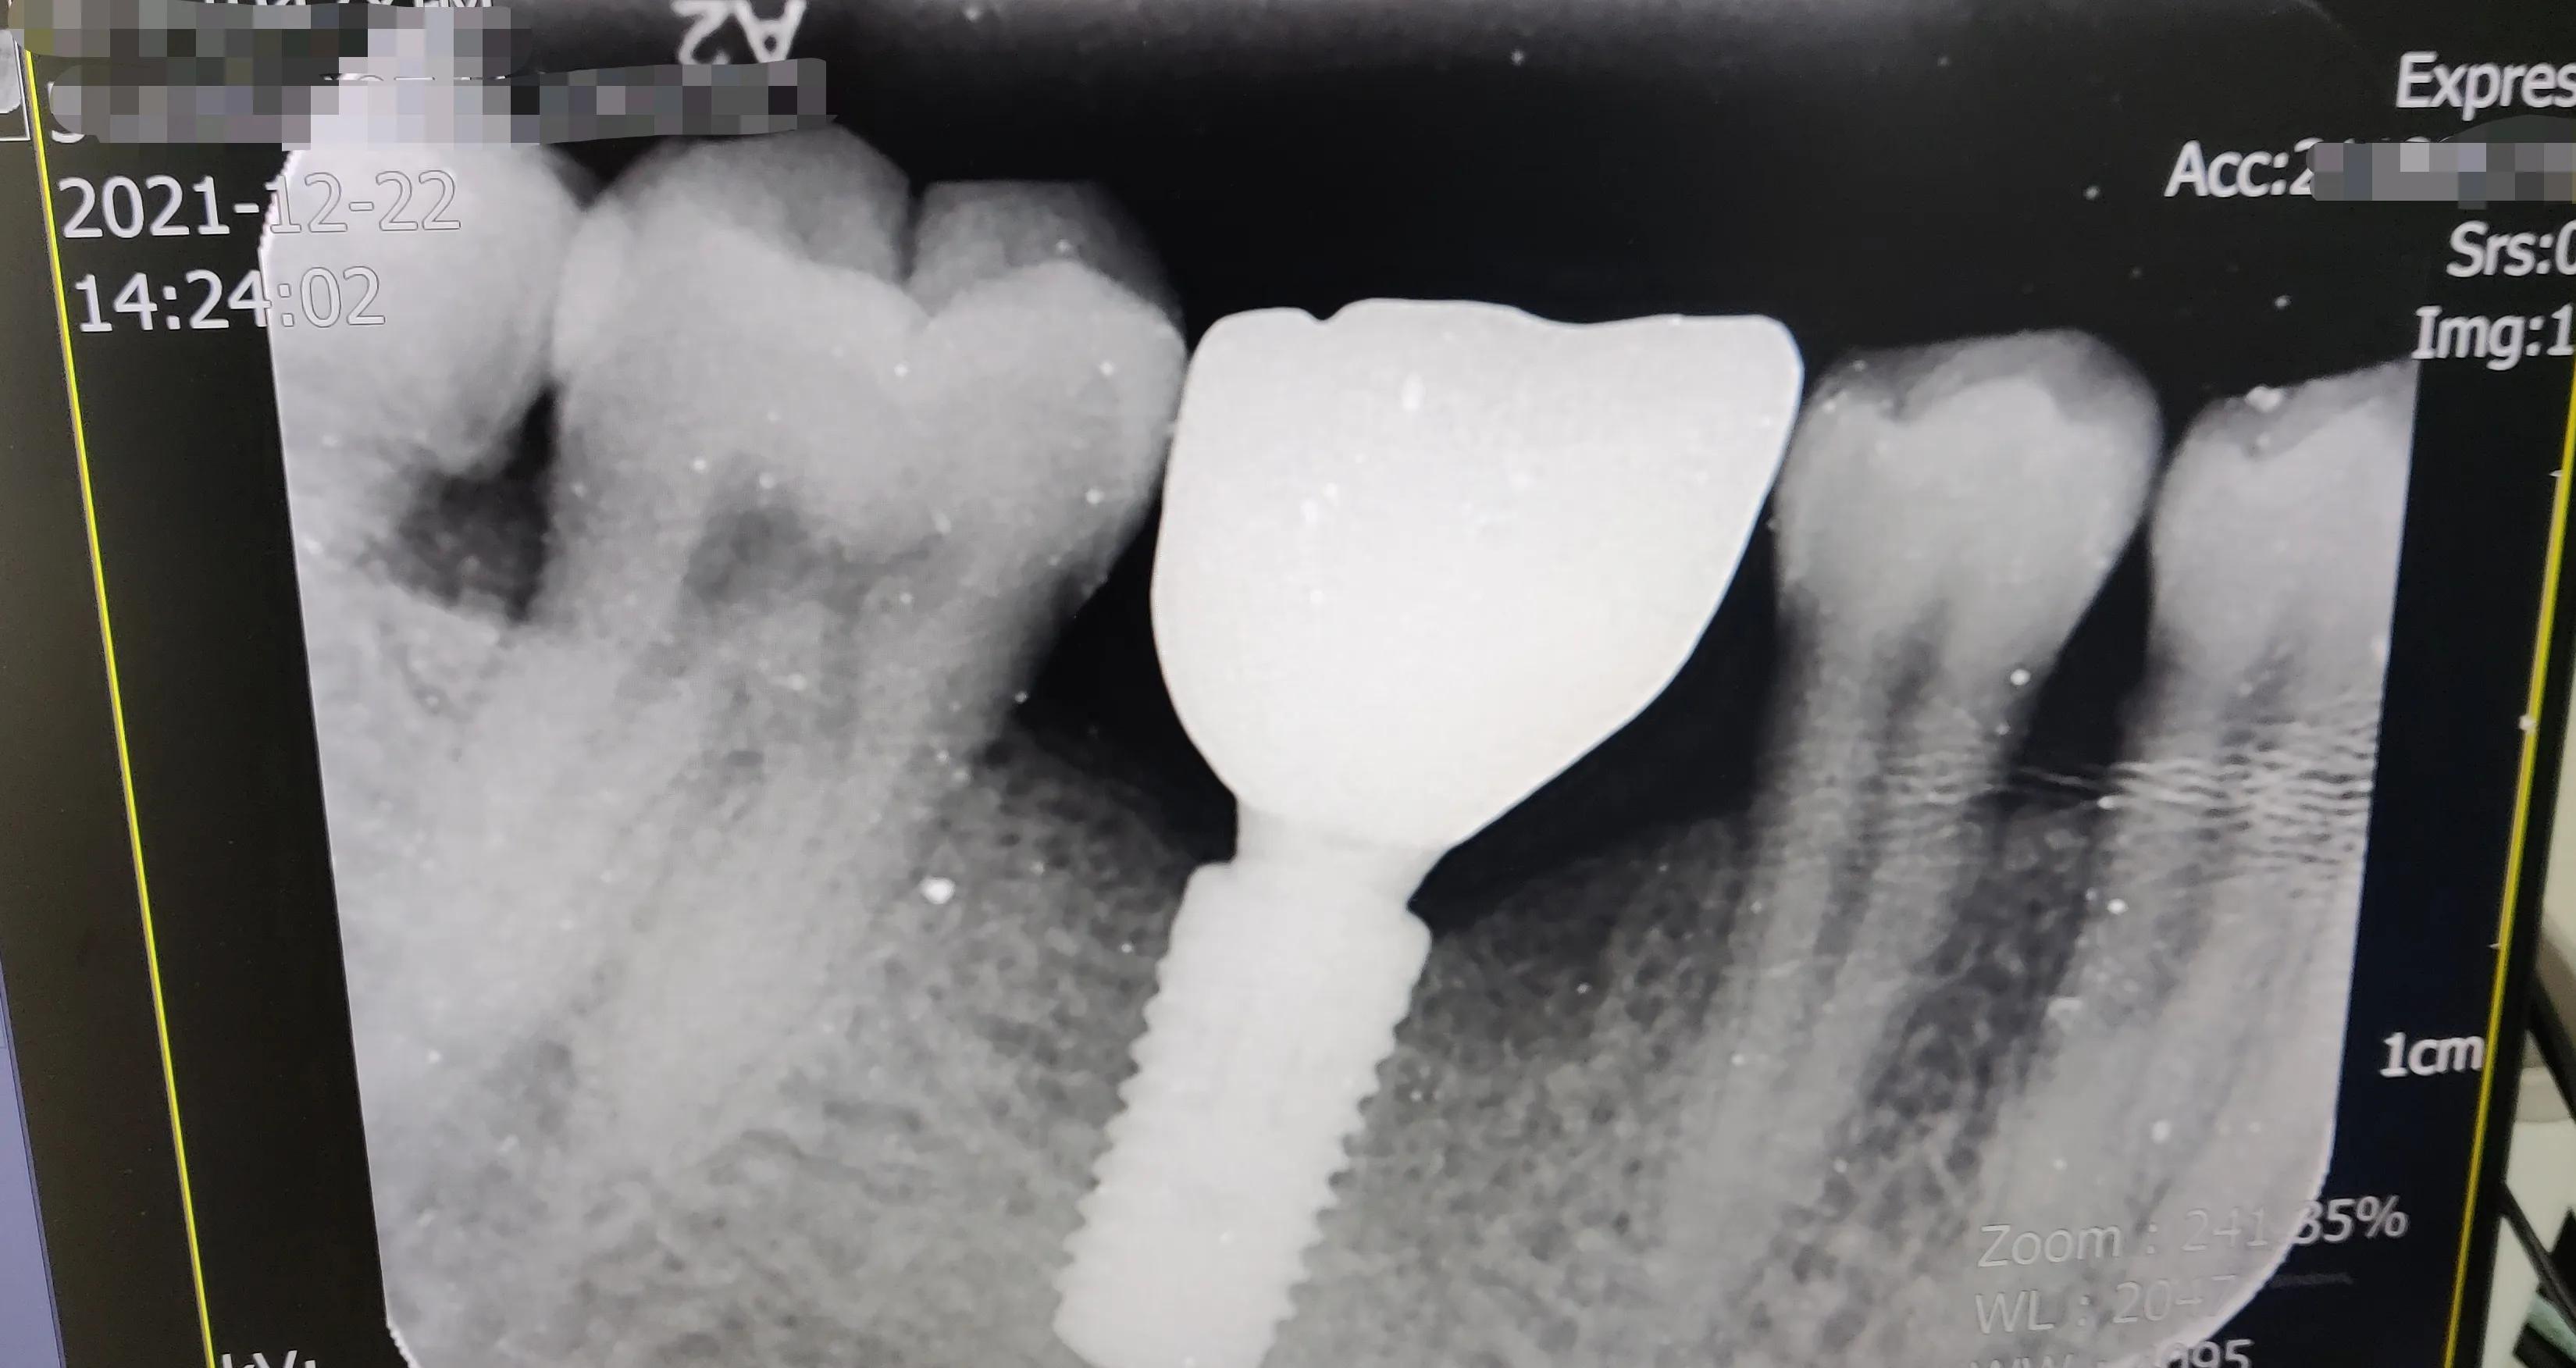

安裝好的片子

真假牙齒在X光片下“原形畢露”哈哈??!